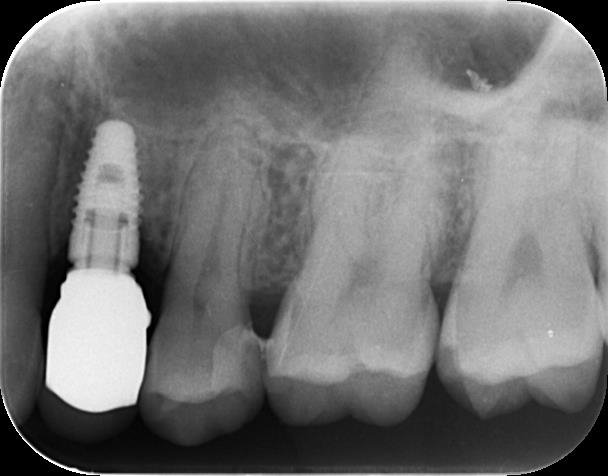

左上のデンタル写真